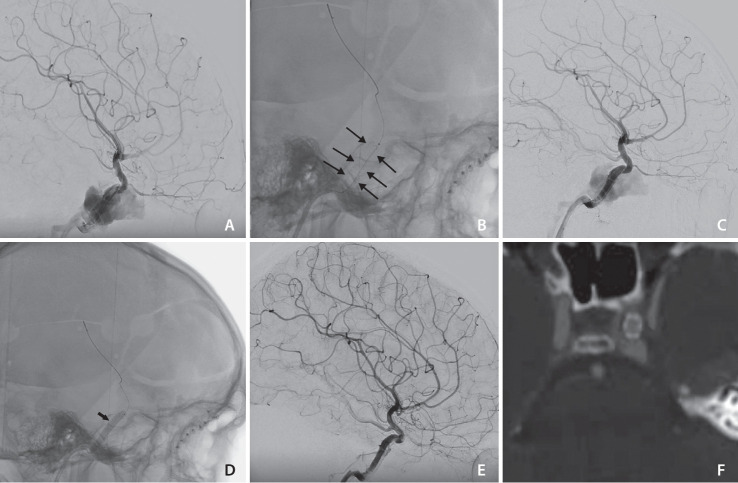

The widely accepted option for treating traumatic direct carotid-cavernous fistula (dCCF) has been endovascular treatment using detachable balloons, coils, or embolic agents. Covered stent deployment has been applied by a few operators and has shown promising results. This is a retrospective study on patients with dCCF treated by an endovascular approach using BeGraft, a covered stent. In 4 cases, this device was successfully deployed without any complications. Immediate complete occlusion was achieved in 3 patients (75%) after deployment of the covered stents. One patient required transvenous coiling for occlusion of the remaining endoleak. Follow-up imaging demonstrated 100% fistula occlusion with complete internal carotid artery patency. No early or late complications occurred following treatment. In conclusion, the BeGraft-covered stent could be a promising safe and effective alternative option for the endovascular treatment of dCCF.

治疗外伤性颈动脉-颈静脉直瘘(dCCF)的公认方法是使用可拆卸球囊、线圈或栓塞剂进行血管内治疗。有盖支架置入术已被少数操作者采用,并显示出良好的效果。这是一项回顾性研究,研究对象是使用有盖支架 BeGraft 进行血管内治疗的 dCCF 患者。在 4 个病例中,该装置被成功植入,未出现任何并发症。有 3 名患者(75%)在使用覆盖支架后立即实现了完全闭塞。一名患者需要经静脉卷曲以堵塞剩余的内漏。随访成像显示瘘管100%闭塞,颈内动脉完全通畅。治疗后未出现早期或晚期并发症。总之,BeGraft 包覆支架有望成为血管内治疗 dCCF 的一种安全有效的替代选择。